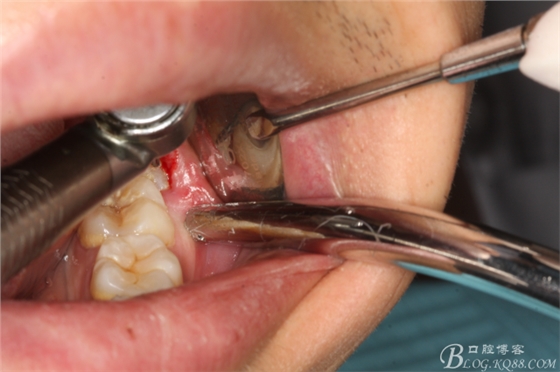

圖4.采用不切開(kāi)、不翻瓣、利用暴露出來(lái)的牙冠進(jìn)行潛掘式分牙